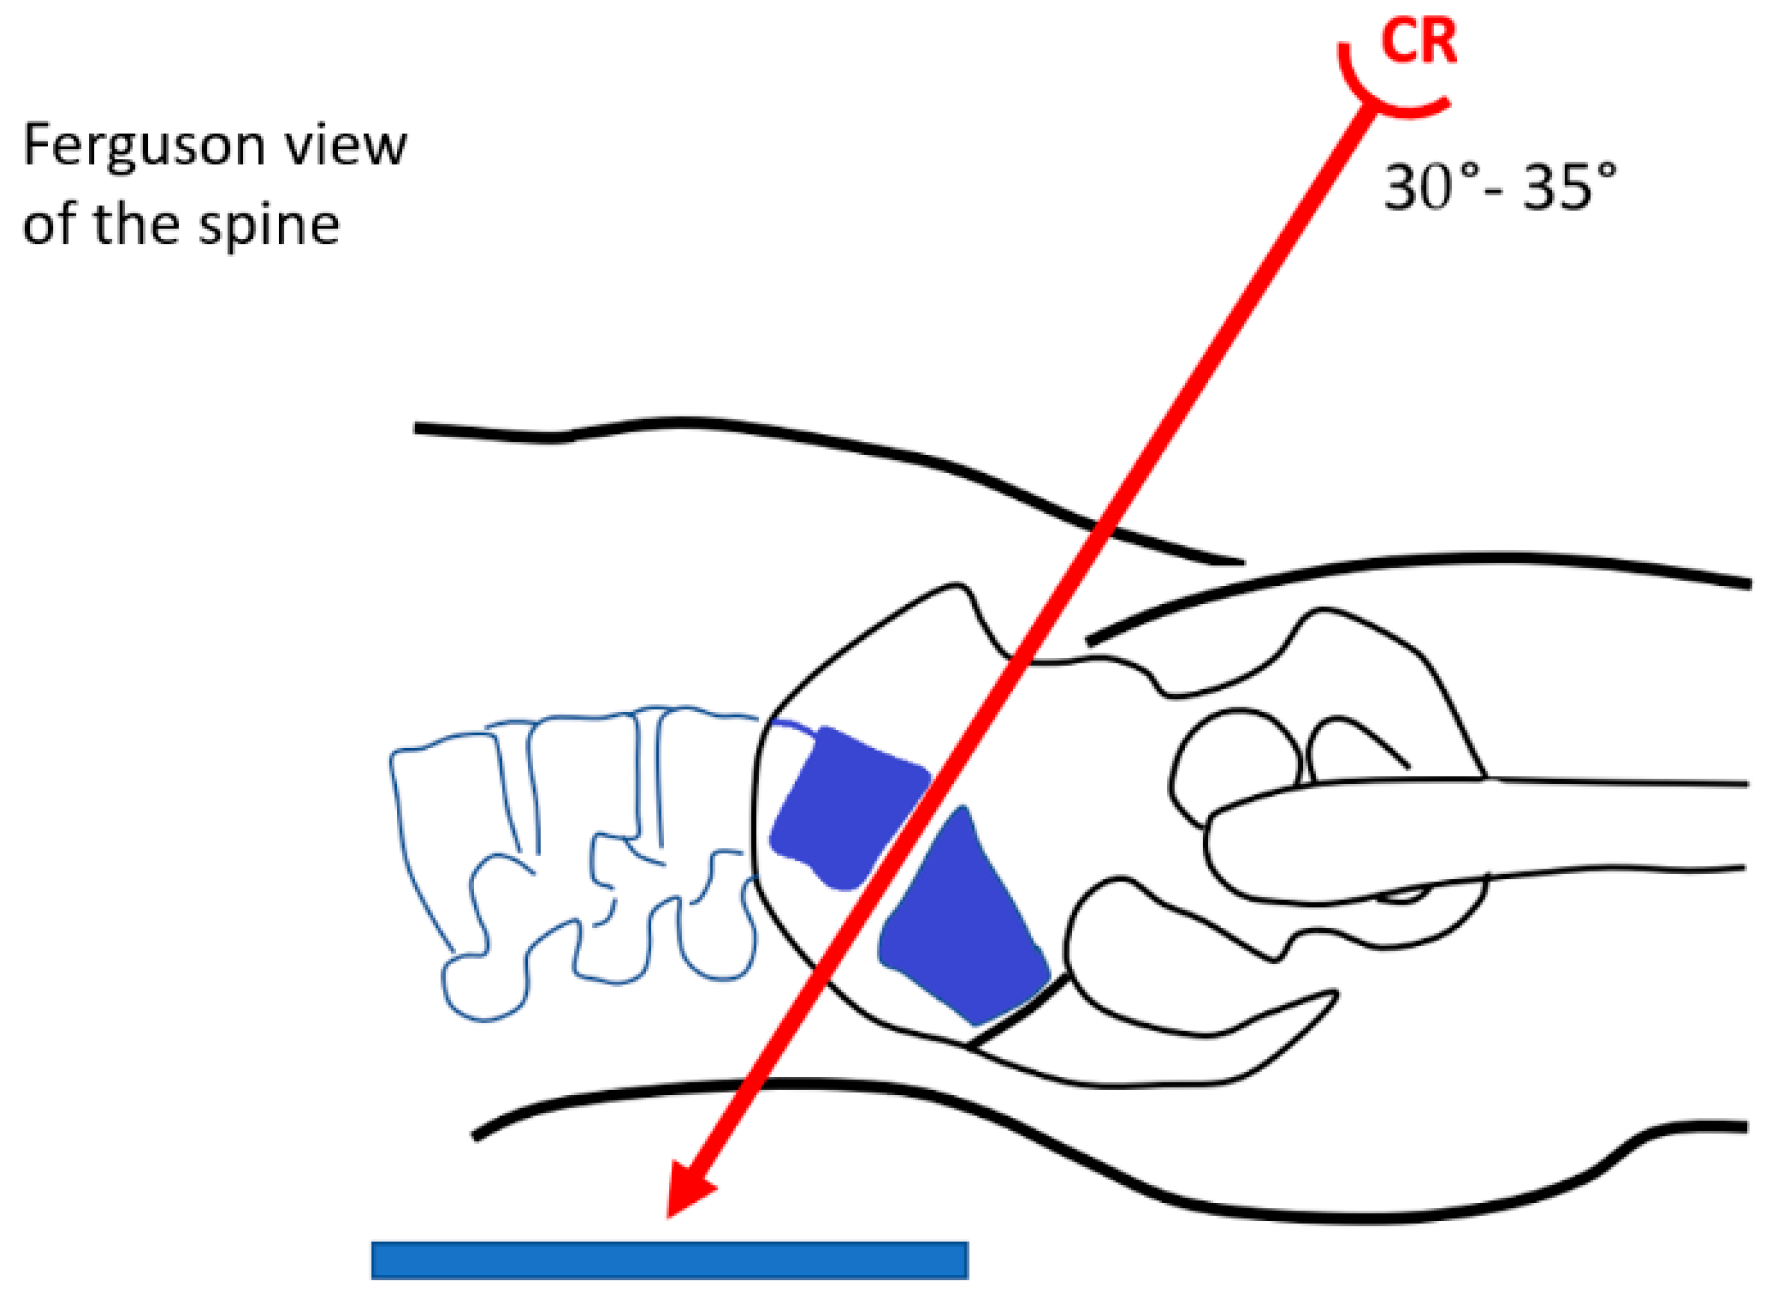

3.4. VMVM Vertical Mid-Vertebral Angle and Diff-VMVA in the Lowest Vertebral Segments

| Vertical Mid-Vertebral Angle | |||

|---|---|---|---|

| VMVA S1-L5 | 30.2° | n-72 | |

| VMVA L5-L4 | 18.8° | n-72 | |

| Diff-VMVA | 11.5° | n-72 | |

| Castellvi Classification | |||

| IIA | Diff-VMVA | 12.4° | n-54 |

| IIB | |||

| IIIA | Diff-VMVA | 9.3° | n-16 |

| IIIB | |||

| IV | Diff-VMVA | 5.5° | n-2 |